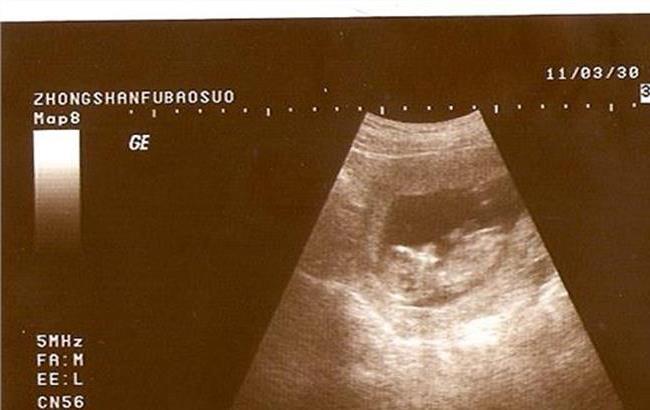

可在月经延迟7天后,可用"孕早知试条"测试尿液,若为很有可能怀孕,"孕早知试条"呈阴性则反之。但如果是怀孕也会有其它的一些症状如,恶心、等。当然最后的办法是到医院做B超检查。